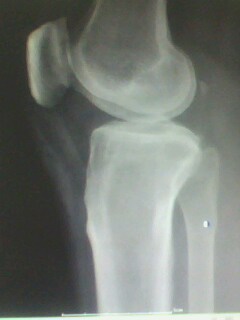

以下是引用muzi888在2010-5-12 11:02:00的发言:[br]骨岛,髁间棘及胫骨关节面有骨增生改变,余无异常。

以下是引用随光逐影在2010-5-12 14:43:00的发言:[br]1)胫骨上段骨岛。2)膝关节退行性改变。